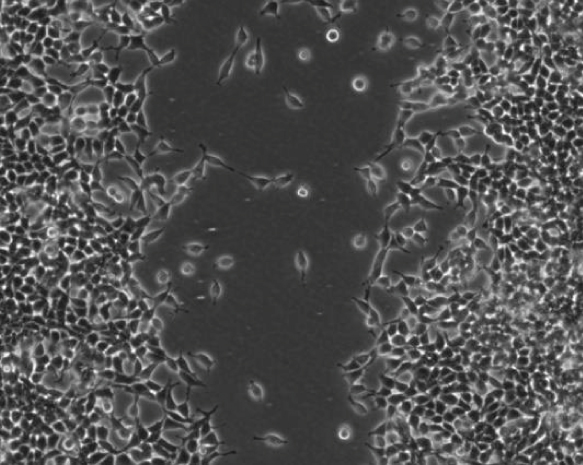

3.5. Wound-Healing Model: Proliferation and Migration

Evidence indicated that metformin suppresses tumor cell proliferation and migration [39–41]. We used a wound-healing model to investigate the effect of metformin on HEK293/TLR4 cell proliferation and migration (Figure 4). The images of the wound-healing model were shown in Figures 4(a), 4(b), 4(c), 4(d), 4(e), and 4(f). Ten distances between the boards of the scratch were measured. The relative distances were expressed as percentage to the distances of the untreated cells (Figure 4(g)).

(a)

(b)

(c)

(d)

(e)

(f)

(g)

The relative distances of the LPS-stimulated cells pretreated with 0, 0.1, and 1 mM metformin were 97.29 ± 8.205%, 110.6 ± 10.75%, and 111.3 ± 6.779%, respectively. No significant difference was observed among those groups of cells. The relative distance of the LPS-stimulated cells pretreated with 10 mM metformin was 158.7 ± 4.323%, exhibiting a significant difference compared to that of the cells treated with LPS only (). Interestingly, the cells treated with 10 mM metformin (only) had a relative distance of 139.9 ± 1.087%, which was significantly different with the cells treated with LPS only (). Accordingly, we concluded that high dose of metformin (10 mM) suppressed either proliferation or migration, or both proliferation and migration of the HEK293/TLR4 cells. However, this inhibitory effect of metformin on the cell proliferation and migration may be independent from the suppressive effect on the transcription factor NF-κB, which required further investigation.